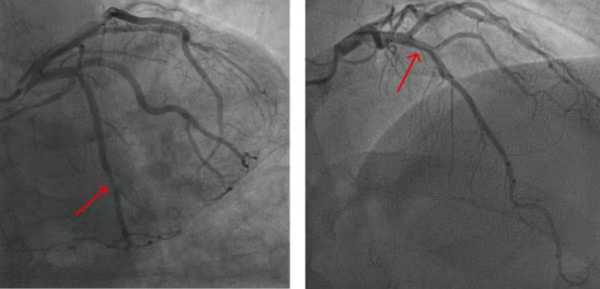

Серцево-судинні захворювання фізично проявляються по-різному у жінок і чоловіків, зокрема, у вигляді бляшок на стінках артерій, що сприяє захворюванню.

У жінок менше кристалів холестерину та менше відкладень кальцію в артеріальних бляшках, ніж у чоловіків. Фізіологічні відмінності в найдрібніших кровоносних судинах, що живлять серце, також відіграють певну роль у серцево-судинних наслідках.

Жінки частіше, ніж чоловіки, мають серцево-судинні захворювання, які проявляються у вигляді множинних звужених артерій, які не повністю «закупорені», що призводить до болю в грудях, оскільки кровотік не може достатньо прискоритися, щоб задовольнити підвищені потреби в кисні під час фізичних вправ, подібно до низькопоточного душу. Коли біль у грудях проявляється таким чином, лікарі називають цей стан ішемією та відсутністю обструктивних коронарних артерій. Для порівняння, у чоловіків частіше виникає «закупорка» артерії в концентрованій ділянці, яку можна відкрити за допомогою стента або операції шунтування серця. Варіанти лікування множинних звужених артерій відстають від варіантів лікування типових «закупорених» артерій, що ставить жінок у невигідне становище.

Кровоносні судини не обов'язково повинні бути закупорені нальотом, щоб спричинити серцеві захворювання.

Причини цих відмінностей до кінця не зрозумілі. Деякі потенційні фактори включають відмінності у складі артеріальних бляшок, через що у чоловіків бляшки частіше розриваються, а у жінок – ерозують. Жінки також мають меншу масу серця та менші артерії, ніж чоловіки, навіть з урахуванням розміру тіла.